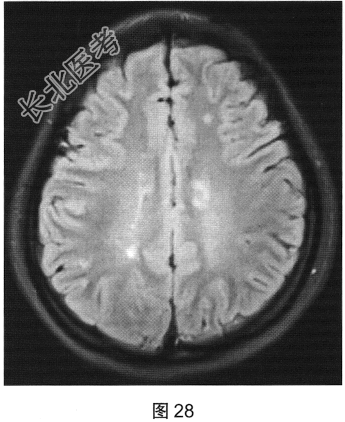

- [材料题] 患者女性,20岁,肢体无力2个月余。MRI检查结果如图27~图30所示。

- 多项选择题1.根据患者MRI平扫和增强的表现,其可能的诊断是( )

F、多发性硬化

- 多项选择题4.关于多发性硬化的诊断,叙述正确的是( )

A、“直角脱髓鞘征”是其较特征性的表现

B、脑内多发脱髓鞘病变

C、脊髓病灶多累及脊髓外周

D、病程呈复发.缓解交替

E、脊髓病灶多位于颈胸段脊髓

F、水肿及占位效应明显